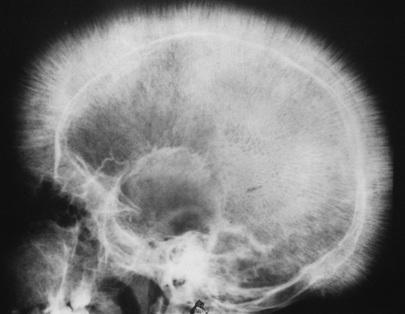

Sometimes additional tests or treatments for iron deficiency anemia are necessary, especially if your doctor. Explain the importance of the diagnostic procedures (such as complete blood count), bone marrow aspiration and a possible referral to a hematologist. Microcytic anemia due to iron deficiency is the most common type of anemia in children.

Anemia is defined as a decrease in the number of red blood cells or the amount of hemoglobin in the blood. The american academy of pediatrics and the world an initial reticulocyte count is needed to determine bone marrow function. Iron deficiency anemia occurs when iron deficiency is severe enough to diminish erythropoiesis and cause the development of anemia. Finding out that you have anemia is just the beginning.